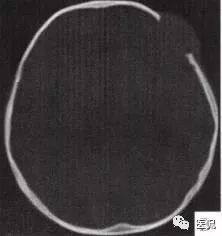

颅脑CT示:图A〜D,CT平扫示左侧额骨、蝶骨见溶骨性骨质缺损,边界清晰,周围无硬化边,伴有软组织肿块向脑外生长,边缘光滑,脑内无明显侵犯;

图H,为颅骨容积重建,提示类圆形骨质缺损,边缘光滑、整齐。

2.定位诊断:额骨、蝶骨均可见局限性骨质破坏,穿破颅骨内外板,见软组织肿块突向脑外;肿块与硬脑膜界限清楚,脑实质无侵犯;应考虑颅骨来源,向颅外侵犯。

②颅骨多处溶骨性破坏,穿透颅骨内外板;

③骨破坏无 硬化边,边缘光整,无膨胀;